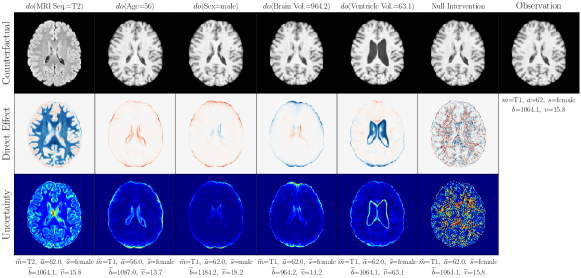

4.2 Brain Imaging Counterfactuals

To demonstrate our model’s ability to produce faithful high-fidelity counterfactuals of real data, we extend our approach to a real-world scenario involving brain MRI scans from the UK Biobank (Sudlow et al., 2015). As before, we start with an assumed causal generative process involving a set of observed variables as shown in Figure 4(a). The causal graph is medically informed and extends the scenario in Pawlowski et al. (2020) by: (i) introducing an additional MRI Sequence (T1/T2) binary variable to enable discrete counterfactuals; (ii) having directly. We used a scaled-up version of our exogenous prior HVAE as ’s mechanism and used (conditional) normalizing flows for the other mechanisms (see Appendix A.1). As shown in Figure 4, our deep SCM is capable of producing qualitatively sharp counterfactuals with localised changes according to the intervened upon parent(s) and the associated causal graph. Importantly, the identity of subjects is well preserved in all cases including null-interventions (i.e. nothing). Table 2 shows the counterfactual effectiveness results from random interventions on each variable. We observed satisfactory initial counterfactual effectiveness and significant improvements of post counterfactual training, demonstrating the merit of the proposed approach. Please refer to Appendix A.2 for notes on abduction uncertainty and D for additional results.